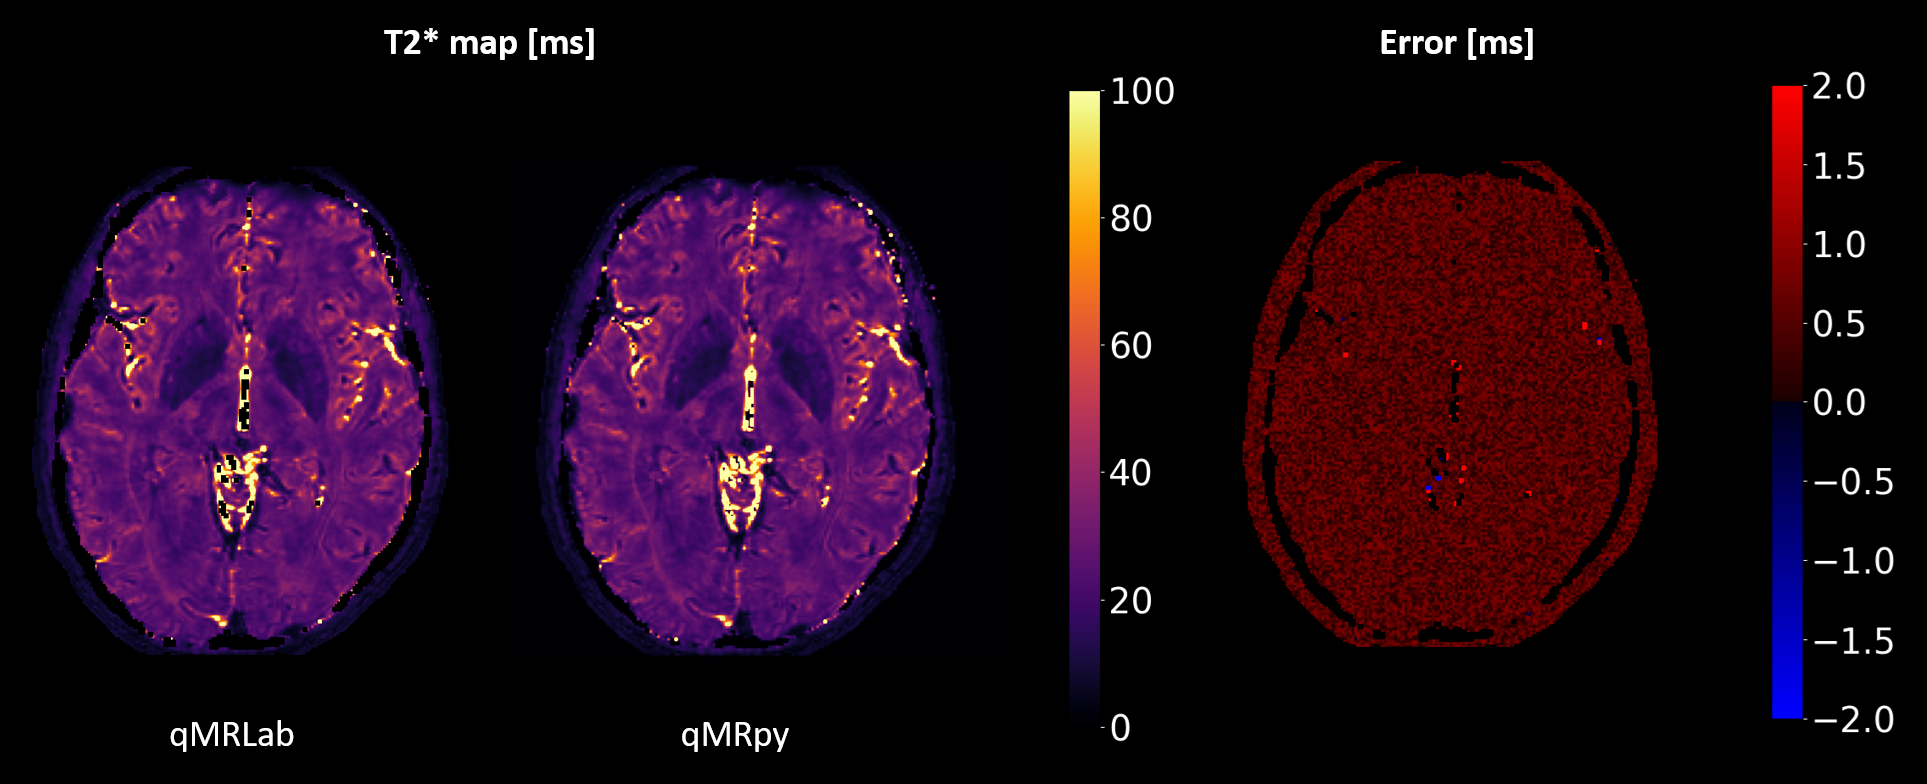

Validation and benchmark: To validate our software, we computed T2* maps from multi-echo Gradient Echo data (whole brain coverage, 200x200x200 matrix size for a 1 mm isotropic resolution, 9 echoes, TEmin = 3.3ms, echo spacing = 3.6ms) of an healthy volunteer, acquired on a GE Healthcare Signa 7T scanner using a 2-channels Tx / 32-channels Rx head coil. As a reference, we computed T2* maps using qMRLab, a flexible and well-established toolbox for qMRI mapping written in MATLAB/Octave. Fitting was restricted to the voxels with a magnitude higher than 5% of the maximum, and the same mask was used both for qMRpy and qMRLab fittings. Quantification accuracy of qMRpy was measured assuming the result of qMRLab as the ground truth, and the two softwares were compared in terms of execution time on a Linux workstation equipped with a 24 cores CPU (with 2 threads per core) and 128 GB of RAM.

Figure 4 shows the comparison between qMRpy and qMRLab derived T2* maps. The two implementations provide the same result, as the voxel wise difference remains below 2ms except for some voxels belonging to CSF where the fit is not well-conditioned. In terms of execution times, qMRpy outperforms qMRLab, reaching an order of magnitude of speed-up thanks to the parallelization enabled by Numba. As the codebase is based on pure Python, without low-level language extensions, the package is easy to customize and to distribute to different platforms, and does not require the purchase of expensive licenses. Thanks to its Command Line Interface, qMRpy-based routines can be easily integrated in automated (e.g., bash-based) pipelines, and its flexible I/O module allows for examination of the reconstructed maps on both vendor-provided and third-party image viewers.

Figure 4. Validation of qMRpy T2* mapping, compared to qMRLab (assumed as ground truth). It can be seen that qMRpy provides correct quantification, the error being less than 2ms in the whole brain mask except for some voxels belonging to CSF where fit is not well conditioned.